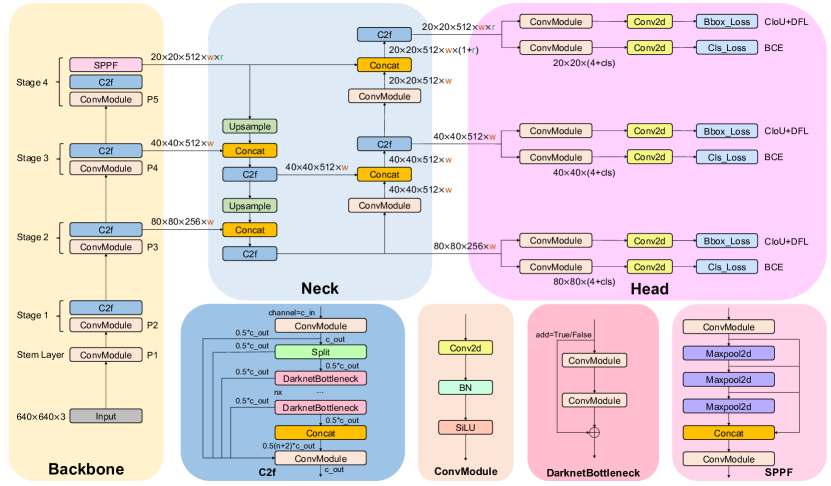

In this section, we introduce the process of the model training, validation and testing on the dataset, the architecture of YOLOv8 model, and the data augmentation technique employed during training. Figure 1 illustrates the flowchart depicting the model training process and performance evaluation. We randomly divide the 20,327 X-ray images of the GRAZPEDWRI-DX dataset into the training, validation, and test set, where the training set is expanded to 28,408 X-ray images by data augmentation from the original 14,204 X-ray images. We design our model according to YOLOv8 algorithm, and the architecture of YOLOv8 algorithm is shown in Figure 2.

Our model architecture consists of backbone, neck, and head, as shown in Figure 4. In the following subsections, we introduce the design concepts of each part of the model architecture, and the modules of different parts.

Backbone

The backbone of the model uses Cross Stage Partial (CSP) [61] architecture to split the feature map into two parts. The first part uses convolution operations, and the second part is concatenated with the output of the previous part. The CSP architecture improves the learning ability of the CNNs and reduces the computational cost of the model.

YOLOv8 [36] introduces C2f module by combining the C3 module and the concept of ELAN from YOLOv7 [32], which allows the model to obtain richer gradient flow information. The C3 module consists of 3 ConvModule and n DarknetBottleNeck, and the C2f module consists of 2 ConvModule and n DarknetBottleNeck connected through Split and Concat, as illustrated in Figure 4, where the ConvModule consists of Conv-BN-SiLU, and n is the number of the bottleneck. Unlike YOLOv5 [53], we use the C2f module instead of the C3 module.

Furthermore, we reduce the number of blocks in each stage compared to YOLOv5 to further reduce the computational cost. Specifically, our model reduces the number of blocks to 3,6,6,3 in Stage 1 to Stage 4, respectively. Additionally, we adopt the Spatial Pyramid Pooling - Fast (SPPF) module in Stage 4, which is an improvement from Spatial Pyramid Pooling (SPP) [62] to improve the inference speed of the model. These modifications lead to our model with a better learning ability and shorter inference time.

Neck

Generally, deeper networks obtain more feature information, resulting in better dense prediction. However, excessively deep networks reduce the location information of the object, and too many convolution operations will lead to information loss for small objects. Therefore, it is necessary to use Feature Pyramid Network (FPN) [48] and Path Aggregation Network (PAN) [63] architectures for multi-scale feature fusion. As illustrated in Figure 4, the Neck part of our model architecture uses multi-scale feature fusion to combine features from different layers of the network. The upper layers acquire more information due to the additional network layers, whereas the lower layers preserve location information due to fewer convolution layers.

Inspired by YOLOv5, where FPN upsamples from top to bottom to increase the amount of feature information in the bottom feature map; and PAN downsamples from bottom to top to obtain more the top feature map information. These two feature outputs are merged to ensure precise predictions for images of various sizes. We adopt FP-PAN (Feature Pyramid-Path Aggregation Network) in our model, and delete convolution operations in upsampling to reduce the computational cost.

Head

Different from YOLOv5 model utilizing a coupled head, we use a decoupled head [33], where the classification and detection heads are separated. Figure 4 illustrates that our model deletes the objectness branch and only retains the classification and regression branches. Anchor-Base employes a large number of anchors in the image to determine the four offsets of the regression object from the anchors. It adjusts the precise object location using the corresponding anchors and offsets. In contrast, we adopt Anchor-Free [64], which identifies the center of the object and estimates the distance between the center and the bounding box.

Loss

For positive and negative sample assignment, the Task Aligned Assigner of Task-aligned One-stage Object Detection (TOOD) [65] is used in our model training to select positive samples based on the weighted scores of classification and regression, as shown in Equation 2 below:

In addition, our model has classification and regression branches, where the classification branch uses Binary Cross-Entropy (BCE) Loss, and the equation is shown below:

The regression branch uses Distribute Focal Loss (DFL) [66] and Complete IoU (CIoU) Loss [67], where DFL is used to expand the probability of the value around the object . Its equation is shown as follows: